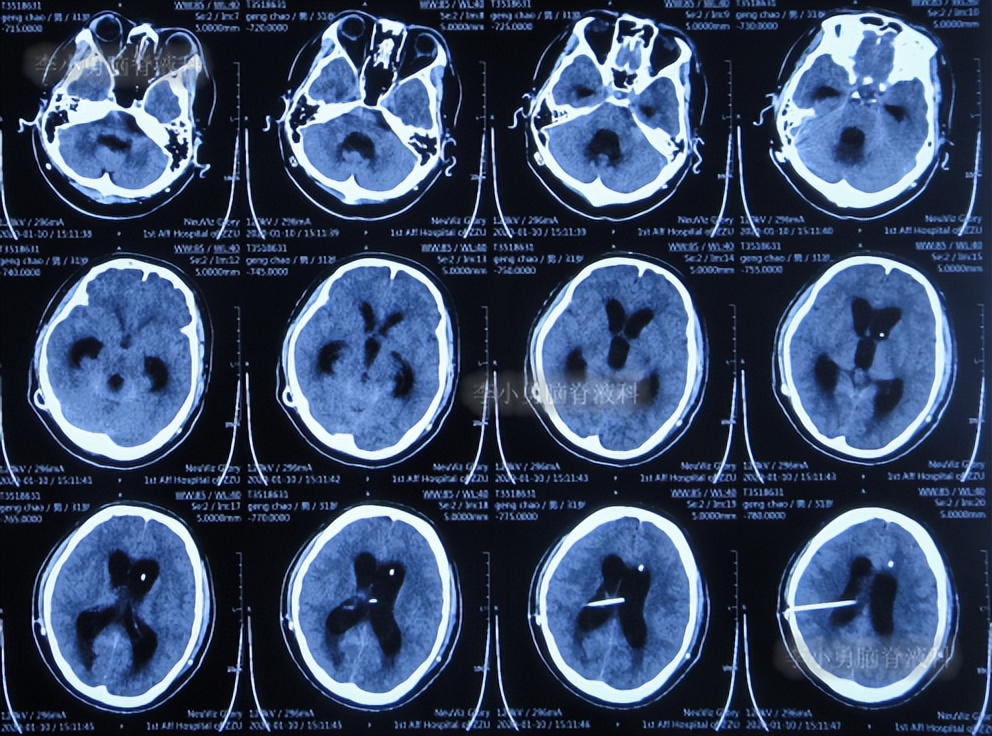

入院次日2019年12月31日,进行了第2次的左侧脑室腹腔分流术(图-6)。

图-6:2019年12月31日头颅CT

第2次的左侧脑室腹腔分流术后10天即2020年1月10日,查头颅CT示脑室仍有扩张(图-7)。

图-7:2020年1月10日头颅CT

第2次的左侧脑室腹腔分流术后18天即2020年1月18日,查头颅CT示脑室有缩小(图-8)。

图-8:2020年1月18日头颅CT